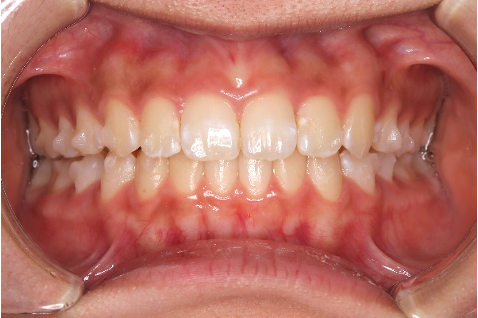

【10代女性】前歯のがたつきを治したい・見た目をきれいにしたい

「前歯のがたつきを治したい・見た目をきれいにしたい」とのことでインビザライン矯正をご希望の患者さんでした。歯並びもキレイになりお喜びいただけておりました。

術後

性別:女性 / 年齢:10代

| 主訴 | 前歯のがたつきを治したい、見た目をきれいにしたい |

| 期間 | 15ヶ月 |

| 費用 | 385,000円 (デンタルローン 3,800円/月) |

| 治療内容 | 治療プラン)ライトパッケージ 治療枚数)28枚 |

| 治療に伴うリスク | 矯正終了後は、リテーナーを指示通りに使用し、歯の後戻りを防ぐ必要があります。 |